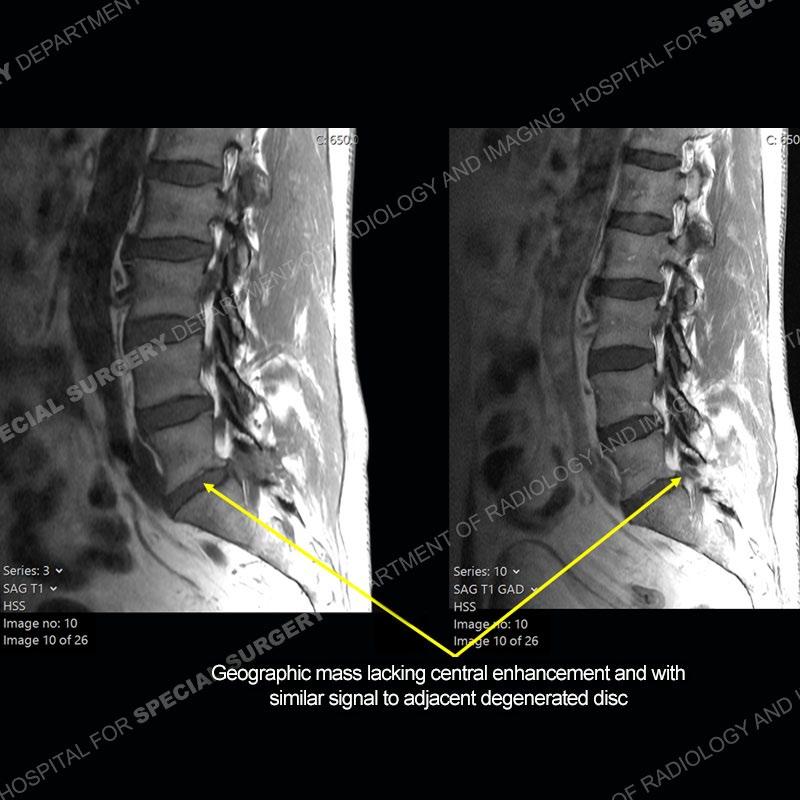

Post operative changes are seen on the left side at L5-S1 where there is near complete removal of the left sided L5 lamina, partial resection of the left L5-S1 facet joint, and resection of the left sided ligamentum flavum. In the anterolateral epidural space about the subarticular recess is a mass that demonstrates similar T1 and T2 signal characteristics to the adjacent degenerated disc. There is enhancement about the periphery of the mass, but the majority of this somewhat geographic or polyploid mass demonstrates no enhancement. The mass exerts prominent mass effect on the left S1 axillary sleeve/proximal nerve root. The left S1 nerve root shows enlargement and increased enhancement as compared to the contralateral right side.

Not as much of a diagnostic dilemma as some other cases but more so just a very nice example of what can be a difficult assessment at times. The evaluation of granulation tissue/scar/epidural fibrosis vs. disc herniation particularly in the earlier post operative period can be very difficult. Clues that can assist in identifying a disc herniation are a more geographic or polypoid nature to the mass, signal characteristics similar to the adjacent degenerated disc, mass effect upon the thecal sac/adjacent neural structures, and a typical enhancement pattern. As the disc material is avascular, as long as imaging is performed in a relatively rapid fashion after contrast administration (within 20-30 minutes), the granulation tissue around the disc will enhance but the disc material itself will not. If there is a marked delay between contrast administration and imaging, there may be diffusion of contrast into the disc making the assessment very difficult. The marked utility of contrast to help delineate disc vs. scar has led to our institution employing contrast fairly uniformly within the first two years following surgery.